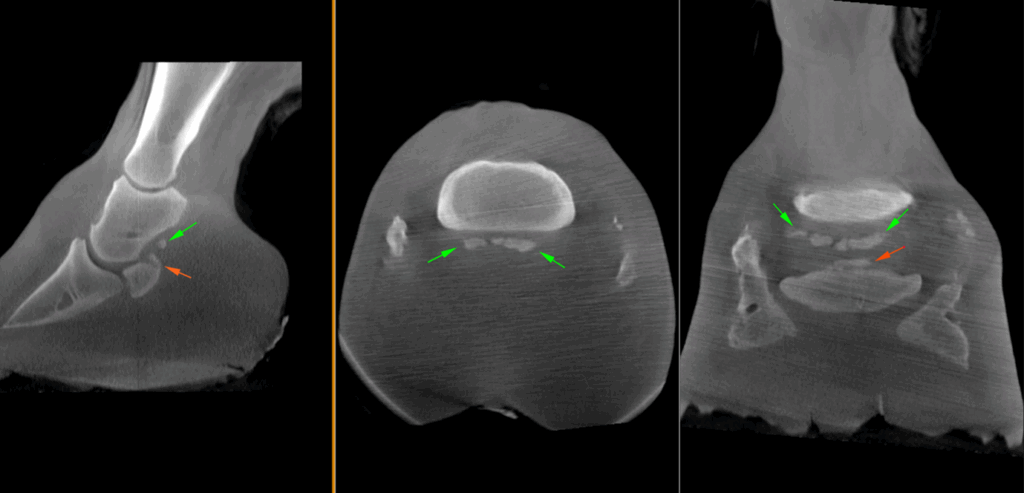

CT findings

The main findings were marked, multifocal mineralization of the collateral sesamoidean (navicular suspensory) ligament, with marked enthesophytes and an avulsion fracture of the proximal aspect of the navicular bone. There was a very small focal region of calcification palmarly to the navicular bone, suspected to be within the deep digital flexor tendon. There was additional marked ossification of both collateral cartilages.

In this particular case of extensive mineralization of the collateral sesamoidean ligament, the horse’s large foot size made imaging with standing MRI unsuitable. As the foot would not fit in the scanner, any resulting images would likely be non-diagnostic. Trimming of the foot was necessary to acquire the CT images. The foot is a complex anatomical structure where radiographs often prove inadequate due to superimposition of structures. Even with additional non-standard views, pathology is frequently underestimated.

Vision CT was considered the ideal imaging modality in this case, as it provides superior visualization of mineralization compared to MRI and enables 3D reconstruction compared to radiographs, offering a comprehensive diagnostic advantage. Despite some compromise in image quality due to the size of the foot, a definitive diagnosis was successfully reached.